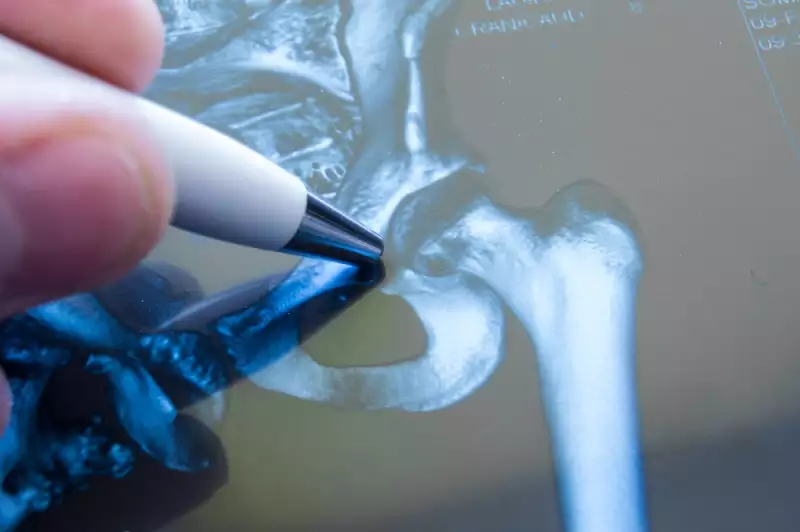

„Dacă ar fi să luăm coxartroza ca exemplu, se pare că riscul femeilor de a face această boală este mai ridicat, comparativ cu al bărbaților. Explicația ar fi o suprafață articulară mai mică și o îngustare mai pronunțată a spațiului articular la femei, spre deosebire de bărbați. Se poate spune că pierderea cartilajului, la femei, poate fi asociată cu vârsta și cu modificările hormonale care apar odată cu înaintarea în vârstă.”, explică dr. Apostolescu.

Anumite date evidențiază că estrogenul, care scade semnificativ odată cu menopauza, are un efect benefic asupra cartilajului articular, lucru demonstrat de terapia de substituție cu estrogeni în postmenopauză care protejează femeile în vârstă împotriva artrozei șoldului.